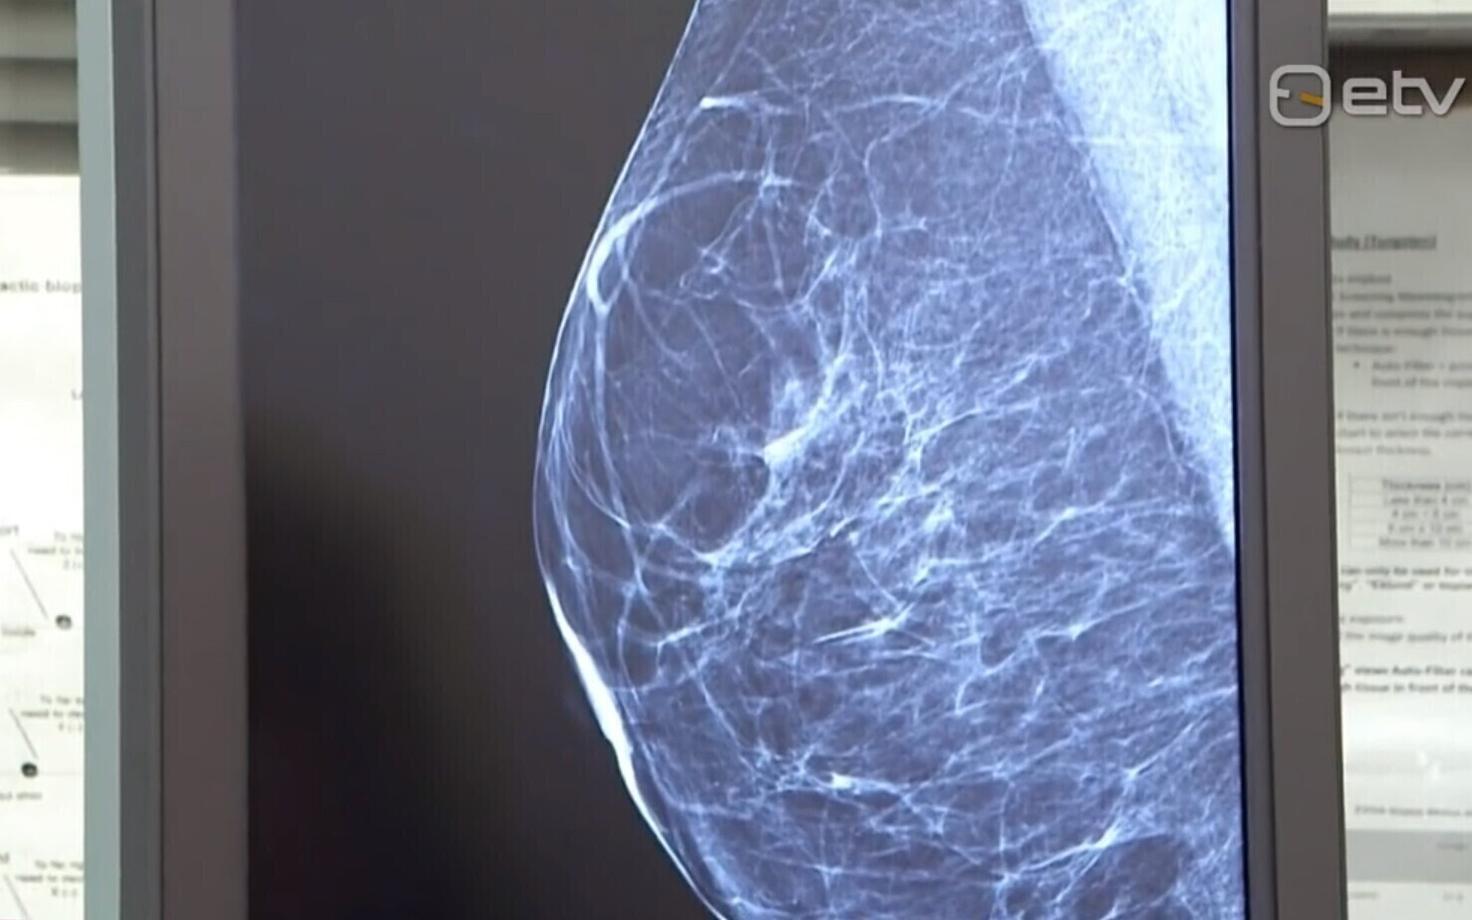

В начале ноября наибольшее количество участников - в скрининговых обследованиях по выявлению рака груди (54 %), теперь гораздо проще зарегистрироваться на этот вид скрининга. Если раньше через дигитальную регистратуру можно было записаться лишь в несколько клиник, то сейчас к системе дигитальной регистратуры присоединилось значительно больше клиник. Скрининги по выявлению рака толстой кишки и рака шейки матки посещали реже, уровень участия в данных обследованиях составляет соответственно 46% и 41%.

- На обследования по раннему обнаружению рака груди приглашаются 50-69-летние женщины 1955, 1957, 1959, 1961, 1963, 1965, 1967, 1969, 1971 и 1973 годов рождения.